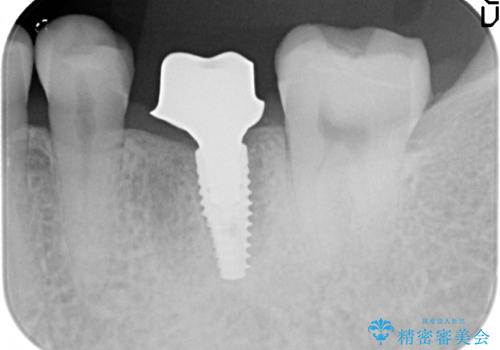

- 左下6の歯で咬むと痛みがあり、たまに膿も出てくるので診て欲しいといらっしゃった方の症例です。

被せ物を外したところ歯が割れており保存不可能だったため抜歯し、インプラントによる欠損補綴を行いました。

当院では主にストローマンという種類のインプラントを治療に用いています。

ストローマンは世界的にもNo1のシェアを誇り、骨との適合にも優れたインプラントです。